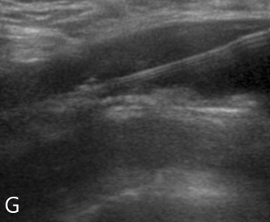

(F, G) Abdominal ultrasound transverse and longitudinal view demonstrated the aortic dissection and guide the fenestration.

Fig 2G